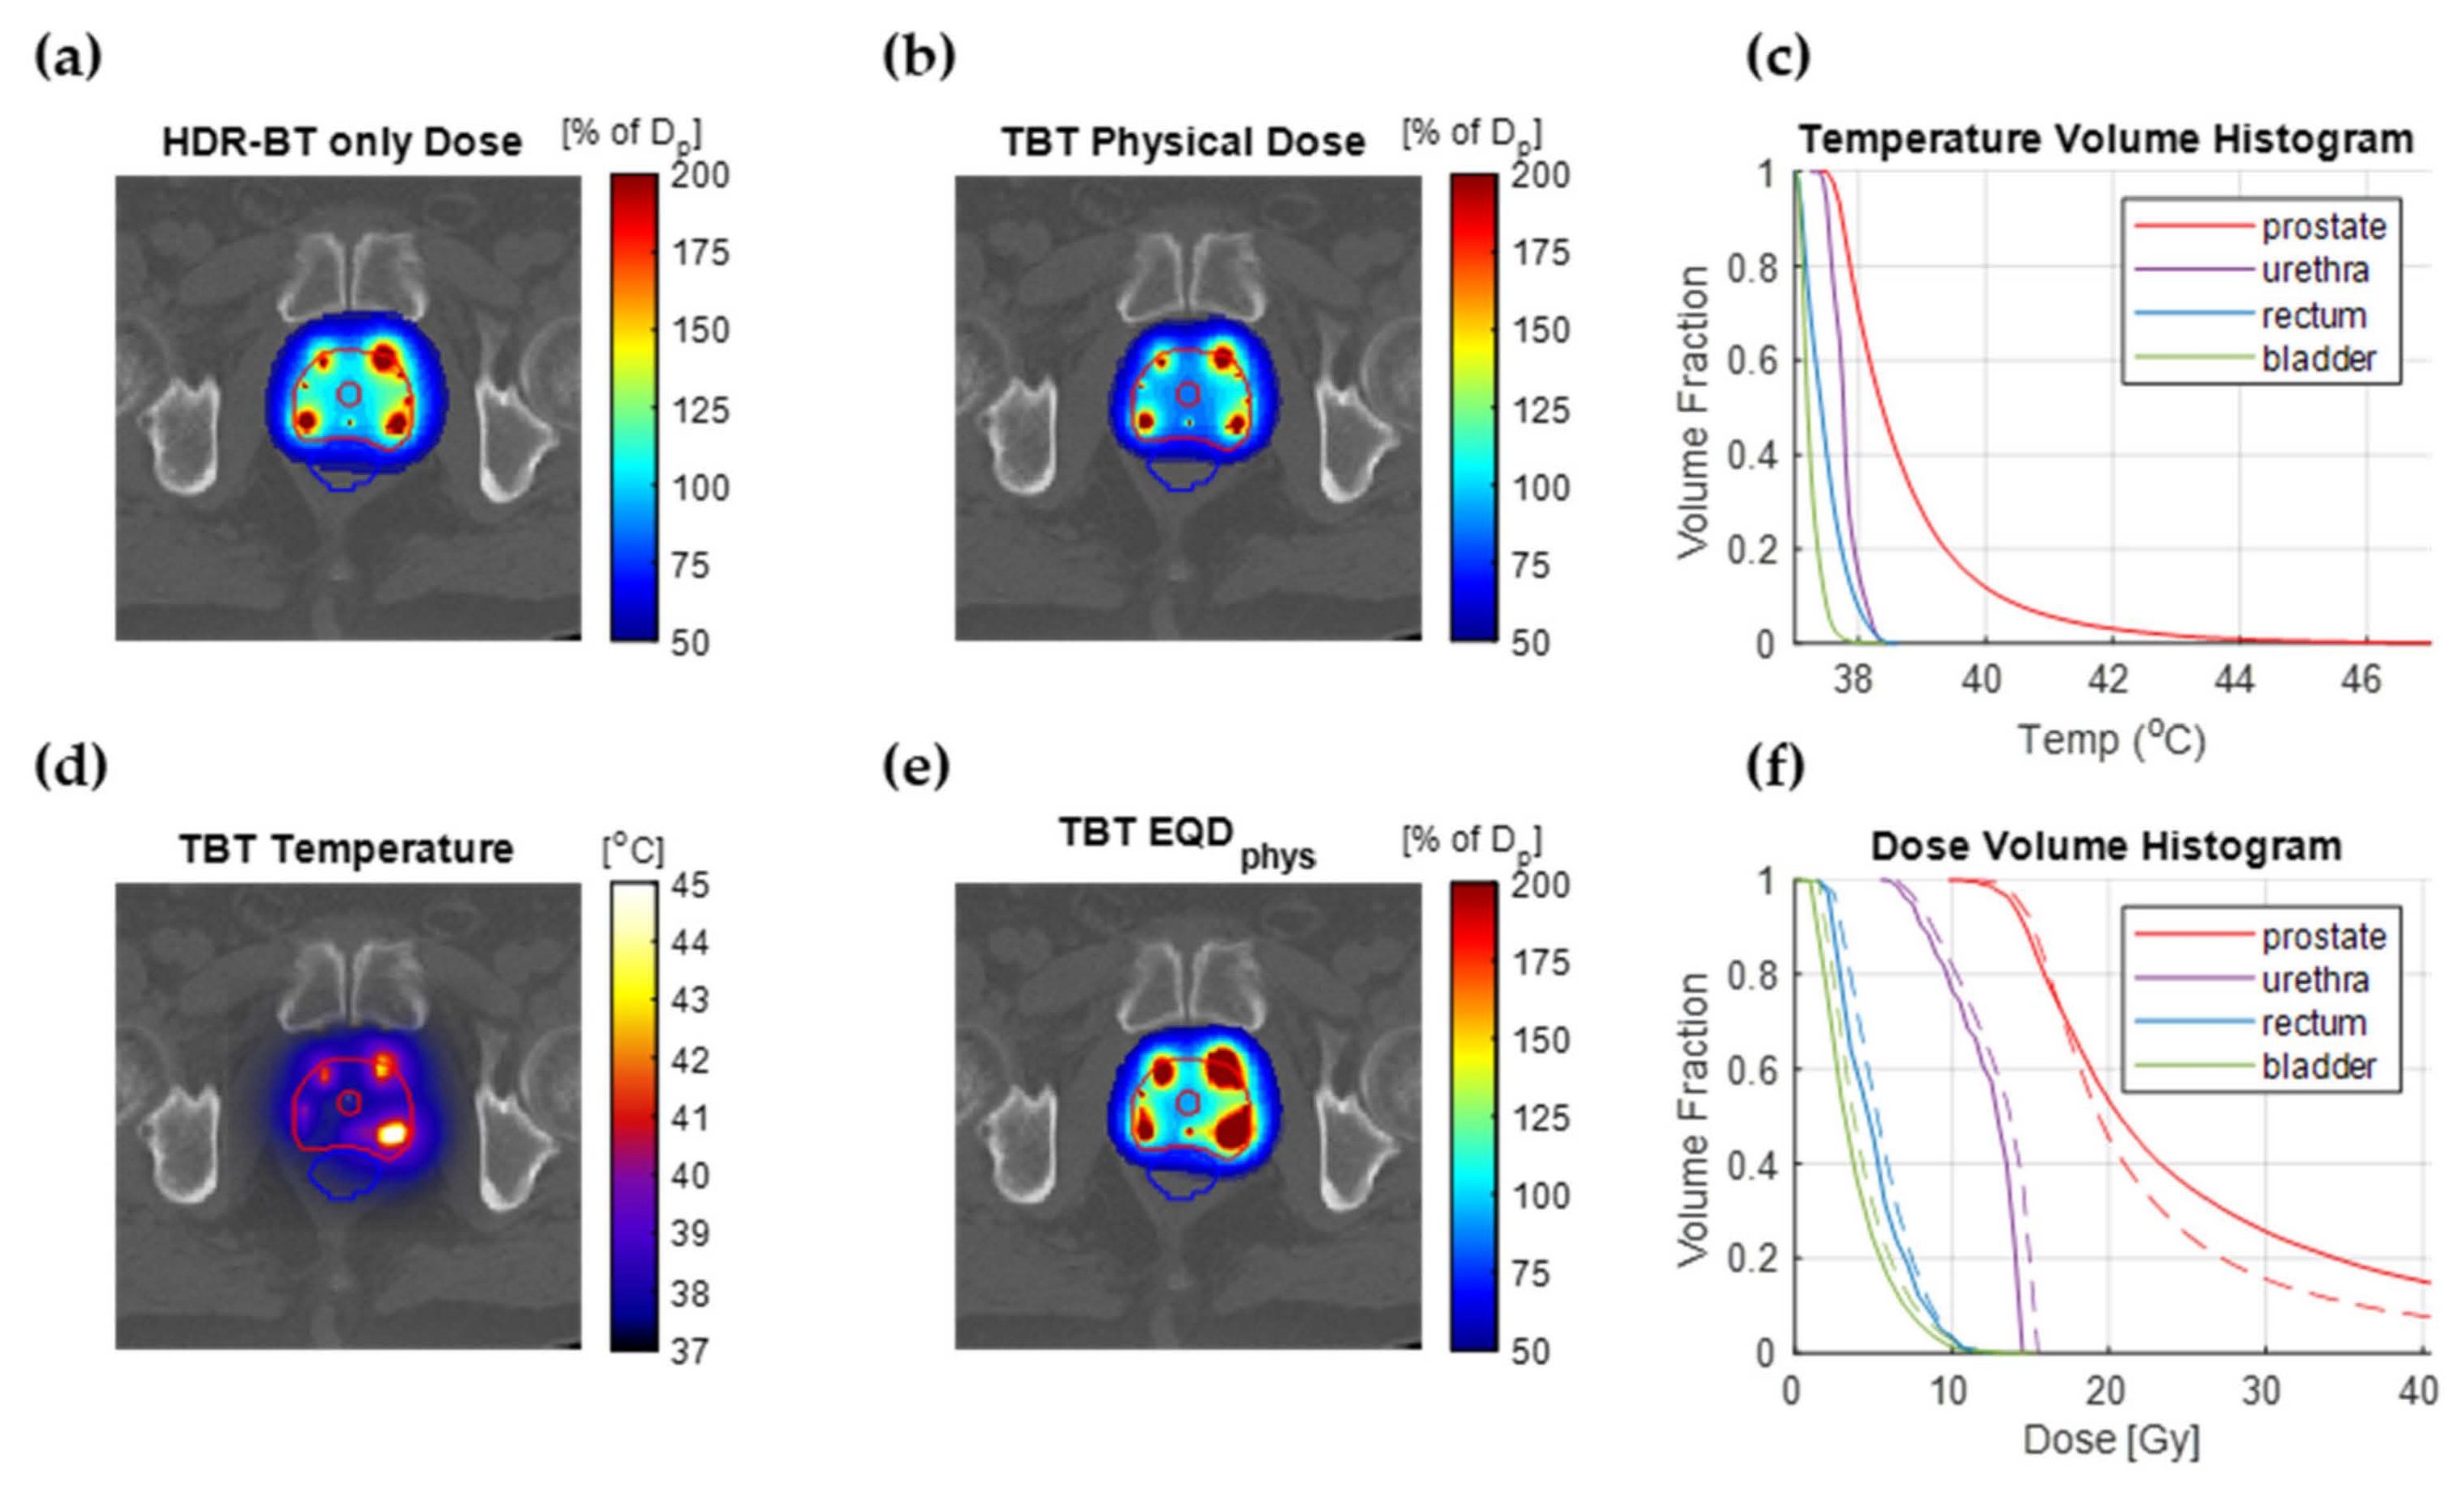

3.3. Treatment Planning Results

4. Discussion